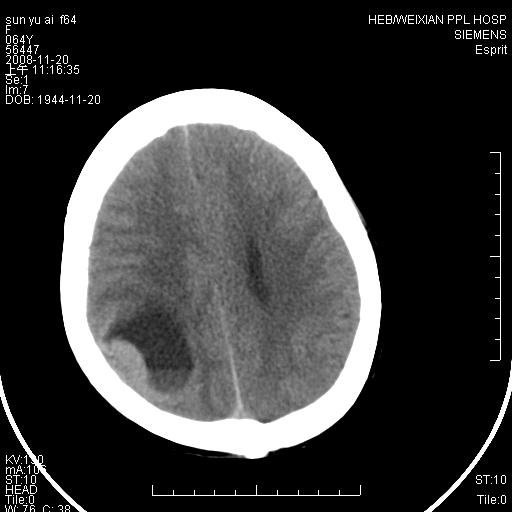

影像表现:侧脑室三角区附近可见以形态不规则的囊实性肿块,其中以囊性成分为主,实性成分为辅,边缘清晰,未见水肿,轻度占位效应,脉络丛钙化向内上移位,右侧脑室轻度扩大(也许体位所致),

1、右侧大脑半球囊实性占位病变,以囊性变为主,实性部分位于病变外后侧,周围无明显水肿,占位征象明显。

2、多考虑胶质瘤可能性大。

右颞顶叶囊实性占位,有壁结节。考虑间变性胶质瘤可能性大,建议增强进一步检查。

囊实性占位,实性部分为等密度或稍高密度,无明显水肿征考虑 -----脑膜瘤或室管膜瘤.其他待排,建议mri 增强检查

右颞顶叶囊实性占位,有壁结节,考虑胶质瘤可能性大,建议增强进一步检查。